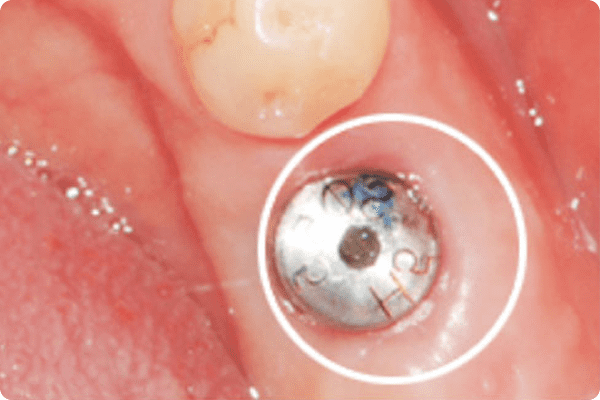

컴퓨터 분석

임플란트수술 당일 붓기·출혈이 거의 없는 모습

잇몸 절개를 하지 않아, 통증이 적고 빠른 회복기존 절개 방식이 아닌 작은 구멍을 통한 임플란트 식립으로 통증이 경미하고 잇몸의 빠른 회복을 돕습니다.

하지만 컴퓨터 분석 임플란트는 잇몸뼈 상태를

파악하기 위해 잇몸을 크게 절개할 필요가 없습니다.

수술 유도장치를 통해 작은 구멍을 낸 후

바로 임플란트를 심을 수 있어 출혈과 붓기,

통증이 적고 수술 후 빠른 회복을 기대할 수 있습니다.